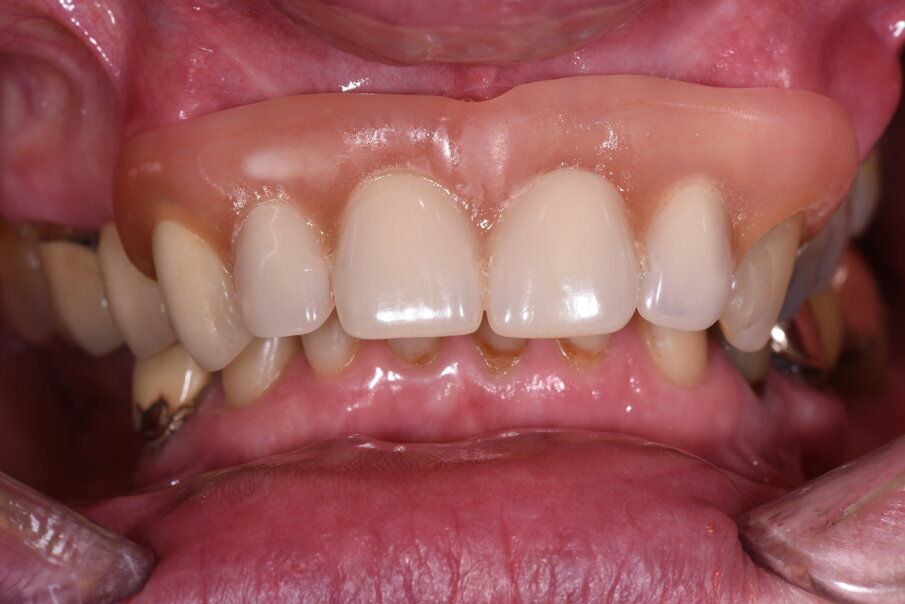

Nell’arcata inferiore dopo il trattamento parodontale abbiamo mantenuto inalterato il V° sestante provvedendo alla rimozione del 3.7 mesio-inclinato con sondaggio e mobilità difficilmente recuperabili e sostituendolo con un impianto. La scelta implantare poco convenzionale ha previsto per la sostituzione bilaterale dei diatorici con impianti in titanio di differente forma e connessione, inserendo bone level (BL) sui premolari e tissue level (TL) sui molari con una protesizzazione mista. La scelta del BL o del TL era rivolta a un aspetto estetico sui premolari e di maggior rispetto tessutale sui molari. Durante le fasi di prova (Fig. 41) si valutano le compressioni dei tragitti transmucosi (Fig. 42), gli eventuali precontatti, si finalizzano le forme e si rileva nuovamente il colore secondo la tecnica di depolarizzazione (Fig. 43). L’appuntamento successivo sancisce l’ottimizzazione dei restauri (Figg. 44, 45). Dopo il posizionamento definitivo dei restauri protesici e l’ottimizzazione dei contatti (Fig. 46) viene nuovamente registrato l’equilibrio di masticazione tramite l’uso del sincronogiografo che registra le forze muscolari confrontando i valori registrati dal momento iniziale pre-trattamento a quello con i provvisori e infine alla stabilizzazione finale, così che nel tempo si possa aver traccia dell’adattamento realizzato (Fig. 47). Il recupero funzionale ed estetico (Figg. 48, 49) rappresentano il traguardo dopo un lungo percorso. Il condizionamento della paziente ha rappresentato un ostacolo nelle libere scelte cliniche segnando di conseguenza l’intero percorso. L’aspetto psicologico ha giocato un ruolo importante nella realizzazione del piano di trattamento, la malattia precedente e il lungo periodo di provvisorizzazione ha arrecato nella paziente un forte disagio. Talvolta quest’aspetto induce il clinico a fare dei compromessi procedurali e anche noi abbiamo cercato di ottimizzare una riabilitazione estetico funzionale correndo dei rischi procedurali a fronte di una richiesta conservativa e talvolta riduttiva nelle procedure chirurgiche. A oggi il follow-up e i controlli di igiene e di verifica della funzione è cadenzato e rigorosamente rispettato dalla paziente. A 5 anni non sono stati evidenziati problemi dei materiali impiegati né tantomeno funzionali (Figg. 50, 51).

Fig. 44_Il momento della consegna rappresenta anche un controllo che deve valutare la cementazione dei monconi l’eventuale presenza di eccessi di cemento, la lucidatura dei punti di contatto e degli spazi interpapillari.

Fig. 45_Il modello digitale rappresenta un mezzo per presentare il restauro nel progetto. È eseguito a computer e solo alcune modifiche vengono fatte, come l’aggiunta di ceramica per enfatizzare l’aspetto estetico. Altro significato è deputato alla precisa posizione degli analoghi implantari.

Fig. 46_Anche la cementazione rappresenta un passaggio importante per l’ancoraggio implantare, il controllo di fissazione dei monconi e la corretta rimozione del cemento.